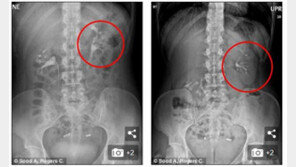

“배가 아프고, 특히 자세를 바꿀 때 몸 안에서 공이 굴러가는 느낌이 들어요.” 최근 영국 데일리메일에 따르면, 나이 이외 신원이 알려지지 않은 한 미국 여성(28)은 6년간 원인 모를 복통에 시달려 왔다. 서 있거나 앉아 있을 때 통증이 심했는데, 임신한 뒤에는 조금 괜찮았다가 아…